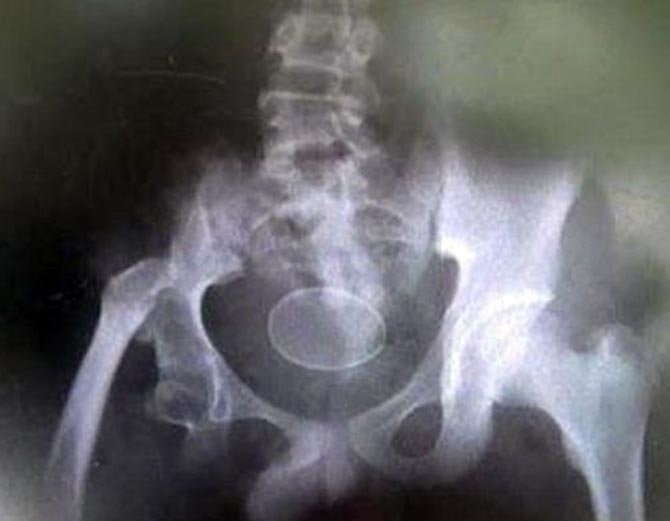

ઘણા X-Ray થયા

આ દાવા સાથે અકમલ અને તેનો પરિવાર પણ એક હોસ્પિટલ પહોંચ્યા જ્યાં અકમલનો X-Ray પણ કરવામાં આવ્યો, X-Ray માં ઈંડું પણ દેખાય છે, પરંતુ ડોકટરો હજુ પણ કંઈ સમજી શક્યા નથી.